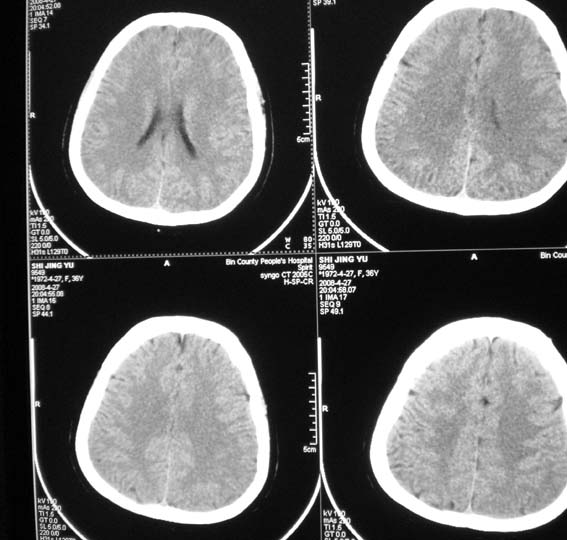

标题: CT13124:女,36岁,常短暂性意识丧失。 [打印本页]

女,36岁,常短暂性意识丧失。

颅脑ct平扫未见明显异常。

右顶部放射冠部白质内异常灰质团块影 考虑灰质移位症可能

患者短暂性意识丧失考虑为癫痫小发作

鞍上池右侧旁脑质内见团块稍高密度影,建议mr检查。